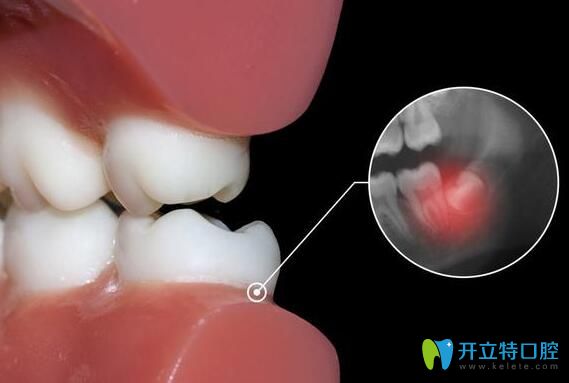

一般長(zhǎng)智齒后,人的牙齦部位會(huì)出現(xiàn)腫痛、發(fā)炎、有的還會(huì)引發(fā)蛀牙等情況,從而影響正常的生活,給身體帶來明顯的影響,這些智齒就需要及時(shí)拔掉了。如果,智齒從萌出到后續(xù)生長(zhǎng)的過程中,沒有出現(xiàn)任何不良癥狀,也是正常發(fā)育,就不需要拔掉智齒了。具體智齒要不要拔,還得看實(shí)際情況而定。

阻生智齒